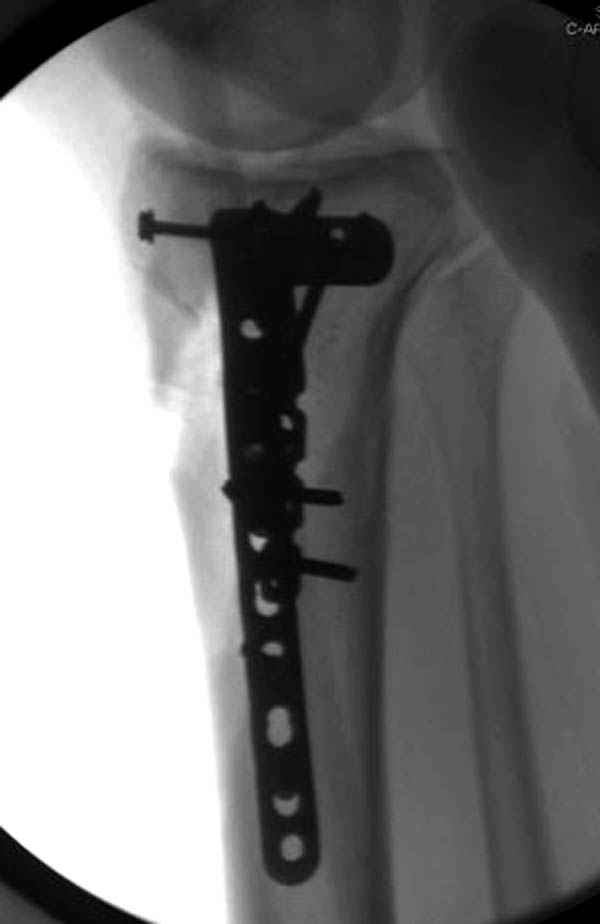

Трудно поверить, что разрекламированная Ортопедическая школа Восточной Украины позволяет такие странные снимки? На прямом снимке сохранен общий контур плато, но не известна судьба импрессии суставной поверхности. На полубоковой?, оставлен без репозиции задне-медиальный отдел, и навряд ли после такой фиксации можно удовлетвориться результатом.

Такая ситуация характерна для многих, когда принимается ошибочное решение, т.е пытаются фиксировать одним имплантом переломы двух мыщелков. Латеральная пластина приемлема только для тех случаев, когда сохраняется интактным медиальный диафизарный кортекс и отсутствует фрагментация на верхушке медиального перелома.

Представленные снимки не информативны, нужны отдельные качественные снимки коленного сустава и голени без ротации.